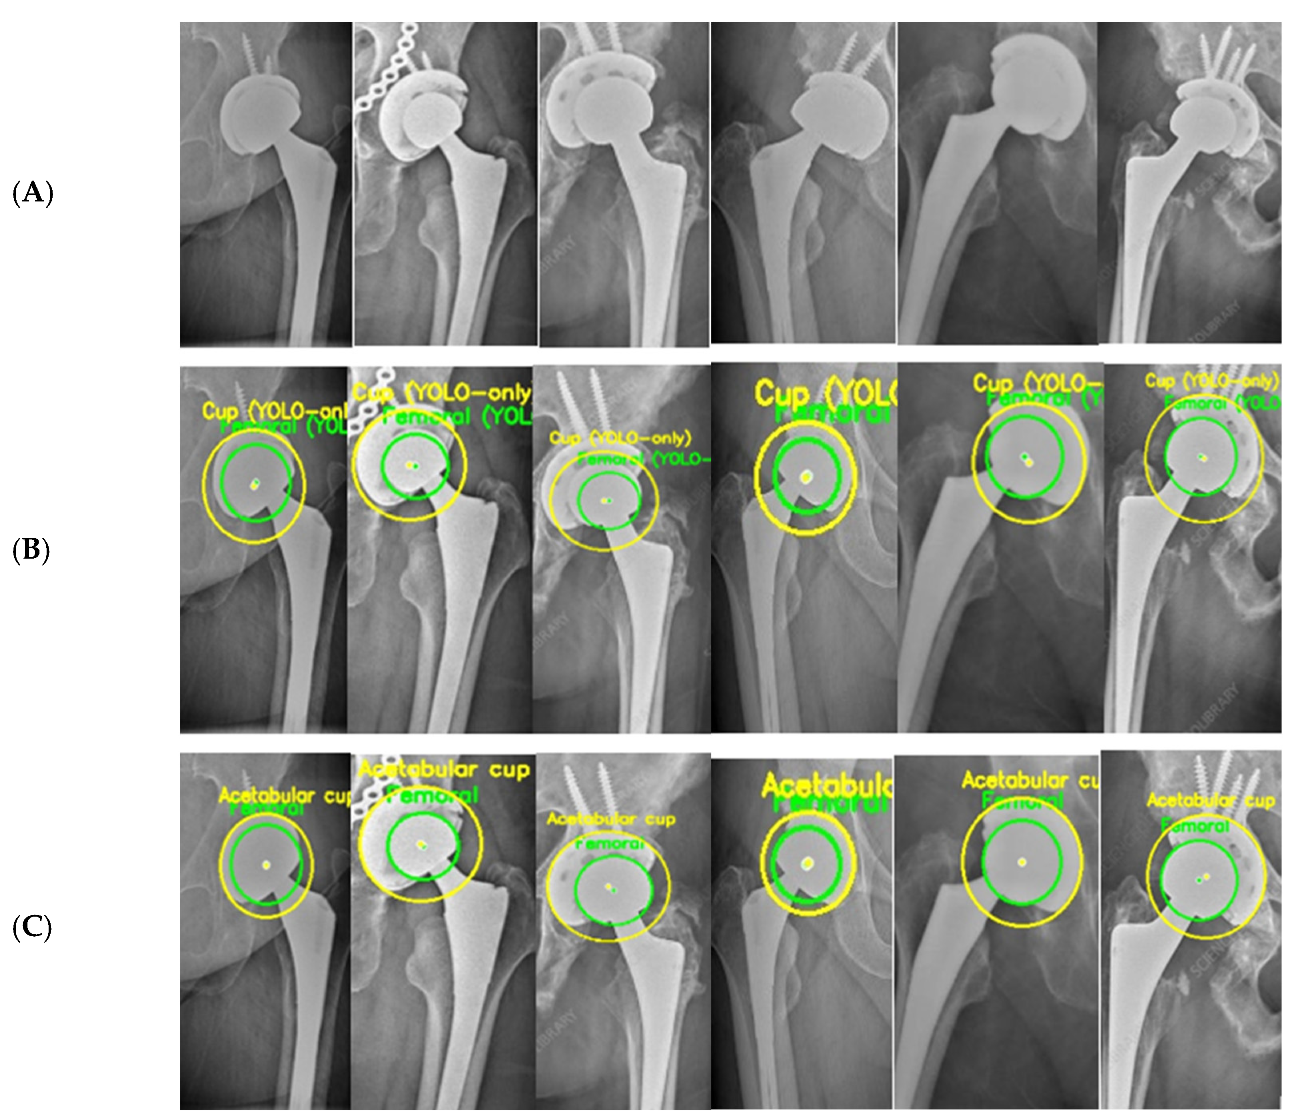

Figure 5 provides a qualitative illustration of the proposed framework on real hip prosthesis radiographs from the external test dataset.

Figure 5.

Femoral and AC Circle Detection Outputs on Hip Prosthesis X-ray Images. (A) shows the original X-ray images, highlighting the variability in implant designs, image quality, and anatomical configurations. (B) presents the intermediate detection results obtained using the YOLOv5-based ROI localization, where coarse circular estimations of the femoral head and acetabular cup are generated. These initial predictions successfully isolate the relevant regions despite challenging conditions such as metallic screws, projection differences, pelvic asymmetry, and partial occlusion of the acetabular rim. (C) displays the final refined circle detections after applying the geometric processing pipeline, including edge detection, Edge-Snap refinement, and RANSAC-based circle fitting. The resulting femoral-head and acetabular cup circles exhibit stable center positions and consistent radii across all examples.

The qualitative results demonstrate the robustness and reliability of the proposed hybrid approach in accurately identifying circular prosthetic components across heterogeneous radiographic conditions. All radiographs shown were exclusively used for testing and were not included in the training or validation stages, confirming the generalization capability of the proposed framework.

Finally, Figure 5 and Table 2 together provide an implicit ablation analysis of the proposed hybrid framework. Figure 5 qualitatively illustrates the progressive refinement behavior from coarse YOLO-based localization to final geometrically constrained circle estimates, while Table 2 quantitatively demonstrates the substantial reduction in error magnitude and variability achieved through geometric refinement when compared with the YOLO-only baseline. The comparative characteristics of manual methods, computer-assisted approaches, and the proposed fully automatic framework are summarized in Table 5, highlighting differences in automation level, user dependence, geometric representation, and computational robustness.